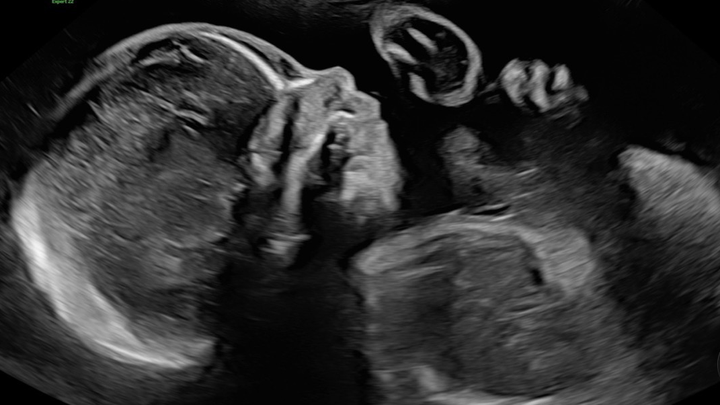

For a while, everything seemed normal. Our doctor’s appointments went smoothly, and each ultrasound filled our hearts with hope and excitement. But as time went on, we received news that changed everything.

After a detailed ultrasound, doctors noticed some serious concerns. We were referred to specialists and eventually sent to UCSF in San Francisco to see some of the best experts in the country. Through countless tests — including fetal heart echos, in-depth ultrasounds, and an MRI — we learned that our sweet baby boy faces many severe complications:

• He has no right lung and only about 10% of his left lung.

• His heart lacks the veins and valves that would normally connect to the right lung and is pushed all the way to the right side of his chest.

• His left kidney is located in his pelvis instead of his abdomen.

• His jawbone is very narrow, causing his tongue to sit farther back in his throat.

• And he has no gallbladder.